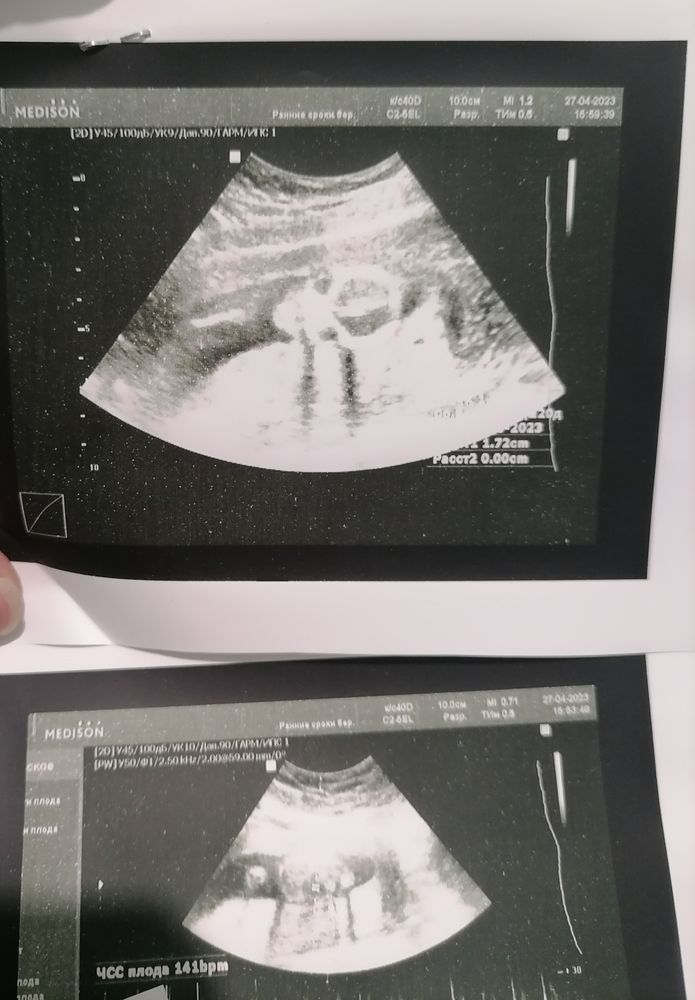

16 недель , кто по вашему?

Пол малышаЭто был плохой аппарат и узистка так себе ) сказала 50/50, а на первом скрининге сто процентов сказали девочка ( аппарат и узистка там были топовые ) А как вы считаете ?

Ракурс не тот, да и качество действительно не очень, поэтому там не разглядеть). Если очень интересно узнать пол, сходите в клинику, в некоторых есть прям услуга "определение пола по узи". Смотрят конкретно пол быстренько, чтобы лишний раз не тревожить малыша долгими узи, да и стоит недорого

Ракурс не тот, голова слева и животик справа, лицом к вам малыш. Может, лежал неудачно и не увидела узистка

Я это узи с черепушкой которое тоже в 16 недель делала, узист сказала, что 90‰ парень будет, а уже в 20 недель на втором скрининге сказали что у нас будет дочь 😅